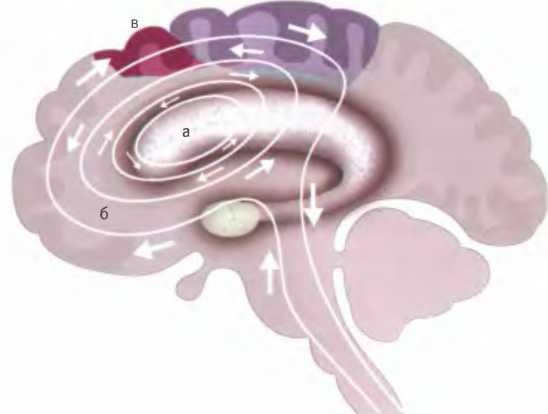

Когда люди, страдающие обсессивно-компульсивным расстройством, оказываются в ситуациях, вызывающих беспокойство, у них в мозгу может запускаться определенный цикл нейронной активности. Он проходит от хвостатого ядра (а), вызывающего побуждение “сделай что-нибудь”, к орбитальной префронтальной коре (б), создающей ощущение “что-то не так”, а затем обратно через поясную кору (в), удерживающую внимание на чувстве беспокойства.

Симптомы ОКР, как и симптомы синдрома Туретта, по-видимому, связаны с гиперактивностью определенных проводящих путей головного мозга. В случае ОКР это пути, соединяющие лобную долю (в том числе премоторную кору) с другой частью базальных ганглиев — хвостатым ядром. Хвостатое ядро соединено со скорлупой и в ходе развития зародыша формируется как единая с ним структура. Главное различие между ними состоит в том, что скорлупа связана преимущественно с премоторной корой, а хвостатое ядро связано с лобными долями, где осуществляются высшие когнитивные функции: мышление, оценивание и планирование. Хвостатое ядро здорового человека присматривает за некоторыми сторонами машинального мышления, точно так же как скорлупа контролирует машинальные движения. Именно хвостатое ядро машинально заставляет нас мыть руки, когда они испачканы, напоминает, что нужно проверить, заперта ли дверь, когда мы выходим из дома, и предупреждает обо всем, что не в порядке, обращая на это наше внимание.

Хвостатое ядро тесно связано с миндалиной, в которой возникают чувства страха и беспокойства. Гиперактивностью хвостатого ядра, стимулирующей активность миндалины, может отчасти объясняться повышенная тревожность, наблюдаемая у людей, страдающих ОКР.

Хвостатое ядро проделывает все это, активируя конкретную область лобной доли — небольшой участок орбитальной коры (расположенной прямо над глазом части лобной доли). Именно эта область активируется у нас в мозге всякий раз, когда мы сталкиваемся с чем-нибудь неожиданным. Этот участок был обнаружен в ходе опытов на обезьянах, которые проводил в Оксфордском университете профессор Эдмунд Ролле. Перед животными зажигали синий и зеленый свет, приучая их ассоциировать синий с наградой в виде фруктового сока, а зеленый — с солевым раствором. После того как они улавливали связь сока с синим, а соли с зеленым, питье меняли местами. Теперь при синем свете обезьяны получали солевый раствор. Когда это происходило, в их мозге сразу же активировалась область, прежде остававшаяся неактивной. Возбуждавшиеся при этом нейроны орбитальной коры реагировали не на соленость: за различение вкусов и чувство отвращения отвечают другие области мозга. Причиной активации данной области было именно неожиданное открытие: что-то не в порядке. Это была реакция, осуществляемая встроенным в мозг механизмом обнаружения ошибок. Когда же обезьяны привыкали время от времени получать при синем свете соленое питье вместо обычного сладкого, такая реакция больше не наблюдалась.

Проведенные впоследствии томографические исследования человеческого мозга показали, что эта область особенно активна у людей, страдающих ОКР. Когда людей с навязчивой склонностью мыть руки просят представить себя в каком-либо грязном месте, их хвостатое ядро и орбитальная кора очень возбуждаются. Сильно реагирует также одна из областей в средней части мозга — поясная кора. Этот участок мозга отвечает за восприятие сознательных эмоций, и его вовлеченность указывает на вызываемый ОКР эмоциональный дискомфорт.